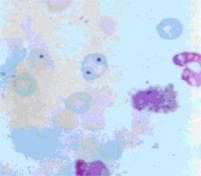

2.2.1 微核試驗 傳統的體內微核試驗仍然是檢測化學物質染色體損傷的基本方法。目前微核試驗方法主要有以下改進:1體外微核試驗 常用細胞有中國倉鼠肺細胞(CHL)、中國倉鼠卵巢細胞(CHO)及中國倉鼠成纖維細胞(V79)等,近年開始有用L5178Y小鼠淋巴瘤細胞和人的類成淋巴細胞TK6。也有用敘利亞倉鼠胚胎(SHE)細胞和BALB/c3T3細胞。體外試驗比體內試驗易於操作和控制。缺點是對直接作用的化合物有可能出現假陽性。2周圍血微核試驗 優點是可重複採樣,自身對照,減少實驗動物數。李尊愛(1999)報導剛斷乳不久的小鼠(4~6周齡)用於外周血網織紅細胞微核試驗比年齡更大的敏感些[16]。3胞質分裂阻滯法微核試驗(CB-MNT) 很好地排除了細胞分裂的影響。該法中,雙核細胞是只分裂了一次的細胞,其結果更加穩定敏感。CB-MNT可觀察到多種遺傳學終點。觀察不同分裂期的細胞比例,計算核分裂指數能檢測誘變物對細胞周期的影響。還可檢測切除修復,次黃嘌呤磷酸核糖轉移酶(HPRT)位點變異,凋亡。認為該試驗可使計數值提高,達到傳統方法的兩倍或以上。但也偶小於兩倍的結果(李來玉,1996)。最近Garriott和Phelps等推薦了關於體外雙核細胞微核試驗的幾個參數條件:細胞鬆弛素B不影響試驗結果;計數2000個雙核細胞;長時間暴露沒有必要;結果用趨勢檢驗分析;根據相應的細胞毒性選擇適當的濃度[17]。

2.2.2 染色體畸變試驗 染色體畸變試驗是檢測化學物質影響染色體數量和結構的基本方法。在化學物質安全性評價中常選體外CHL細胞染色體畸變、精原細胞染色體畸變試驗等檢測化學物質對染色體的影響。為了準確觀察誘發的畸變頻數,本試驗收穫細胞的時間應儘量提前至大多數細胞處於染毒後第1次有絲分裂時(Tucker,1996)。對於染色估數目改變,原則上只適合超倍體的觀察。因為塗片時可能人為地把染色體推出細胞外(Tucker,1997),Danford曾建議在製備標本時減弱低滲處理能力,以免漲破細胞膜,從而能準確觀察亞二倍體。經研究,認為以0.094mo1/LKC1弱低滲液處理2min~3min是達此目的的最佳條件(樓鐵柱,1997)。

2.2.3 螢光原位雜交(FISH)技術 螢光原位雜交最早由Bauman(1980)建立,後由Lucas(1989)首先套用於染色體畸變分析。其原理是按檢測目標準備恰當的DNA序列作為探針,並用生物素標記,對載玻片上待測標本中的DNA雜交,最後通過雜交位點的螢光觀察染色體結構或數目的改變。套用特殊染色體和染色體某區域的螢光探針可在體內檢測4種類型的細胞遺傳學終點[18]。1檢測中期細胞染色體畸變。2套用亞染色體區域的探針檢測間期染色體斷裂和非整倍體。3套用中心粒探針和/或抗著絲點抗體檢測微核的形成。Schriever-Schwemmet等利用CREST間接免疫螢光法,以及小鼠次要和主要衛星DNA探針,在小鼠骨髓細胞證明了受試物引起微核的來源[19]。4哺乳動物精子非整倍體檢測。徐德祥(1999)用雙色FISH方法對丙烯腈接觸男工精子性染色體數目畸變進行了檢測,證明FISH技術用於檢測精子染色體數目畸變實驗結果穩定可靠。

2.3 檢測DNA原始損傷2.3.1 單細胞凝膠電泳技術 單細胞凝膠電泳分析(singlecellgeleletrophoresis,SCGE)是Ostling等(1984)首創的,以後經Singh等(1988)進一步完善而逐漸發展起來的一種快速檢測單細胞DNA損傷的實驗方法,因其細胞電泳形狀頗似慧星,又稱慧星試驗(cometassay)。Kizilian(1999)改進了一些試驗條件,能明顯將細胞調亡和細胞壞死的形象與“彗星”區分。MarkS.Rundell等(2003)報導彗星試驗測行的損傷主要是由致突變劑引起的[20]。RichardD.Bowden等(2003)研究出了一種新的分析試驗結果的彗星尾圖譜,可以更加準確的分析彗星的長度及密度[21]。SCGE是評價遺傳毒性損害非常敏感的實驗,可以檢測到每1.657×10-37kg中0.1個DNA的斷裂。與經典的染色體畸變、微核、SCE相比,SCGE可以用於活細胞DNA的檢測,也能用於死亡細胞DNA的分析,使SCGE不僅可以研究低劑量下的生物效應,也可用於研究高劑量下的生物效應;同時SCGE又可提供DNA修復能力的信息,這使得SCGE非常適用於評價受試物的遺傳毒性[22]。